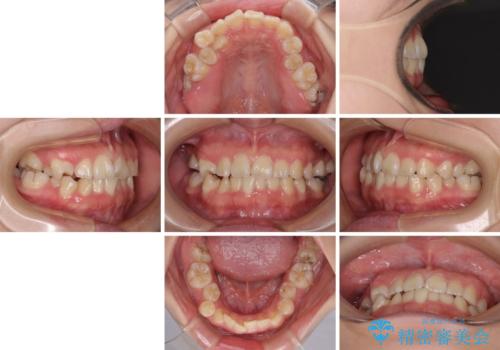

重度叢生と埋もれた奥歯 8本を抜歯したワイヤー矯正

- 内側に生えている歯や埋もれた奥歯を気にして来院された患者様です。

顎の骨が小さいため、歯列が収まりきらずに叢生や未萌出となっている状態でした。

埋もれた奥歯を萌出させ、さらにデコボコを解消するために、上下左右の第1小臼歯4本に加え、親知らず4本も抜歯し、ワイヤー装置にて矯正治療を行うこととしました。